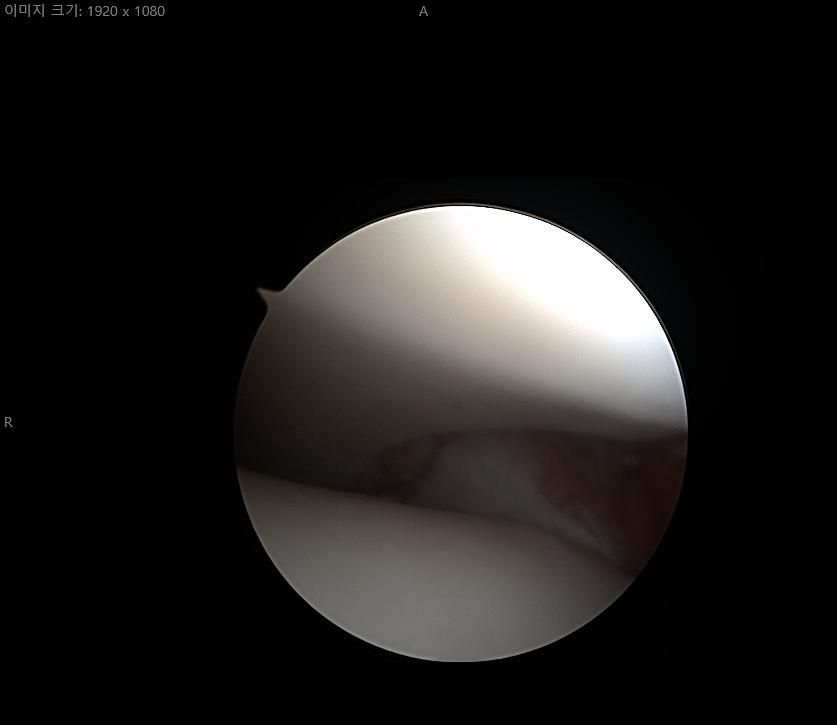

제가 발목 연골손상이라 mri와 내시경 사진이 있는데

어떤 상태인지 좀 다른 고견을 들어보고자 합니다

• 2번 째 사진

현재 연골 손상이 있으신 것으로 보이는데요, 올려주신 사진이 참고에 도움이 될 수 있으나 정확한 소견을 말씀드리기에는 어려움이 있으므로 정확한 소견은 주치의에게 들어보시는 것이 좋겠습니다.